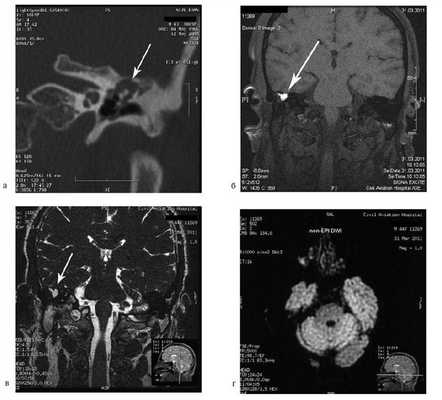

На КТ височных костей справа послеоперационная полость, заполненная мягкотканным образованием, определяется большой костный дефект в направлении сигмовидного синуса и мозжечка (рис. 2, а). Рисунок 2. КТ и МРТ височных костей больной У. с хроническим правосторонним средним отитом. Состояние после радикальной операции (1993 г.), санирующей операции с мастоидопластикой и тимпанопластикой (2003 г.). Холестеатома. Парез лицевого нерва. а — КТ; б — МРТ основания черепа в режиме Т1; в — в режиме Т2; г — в режиме non-EPI DWI.

Больной была выполнена МРТ (рис. 2, б—г).

В режимах Т2 и non-EPI DWI определяется сигнал высокой интенсивности, в режиме Т1 — низкоинтенсивный сигнал. Это может свидетельствовать о наличии холестеатомы мастоидальной полости и пирамиды височной кости. Диагноз: хронический правосторонний средний отит; состояние после радикальной операции в 1993 г. и санирующей операции с мастоидопластикой и тимпанопластикой в 2003 г.; холестеатома; парез лицевого нерва.

Больной произведена санирующая реоперация, в ходе которой удалена холестеатома больших размеров, заполняющая отшнурованную послеоперационную полость. Эта полость распространялась до верхушки сосцевидного отростка, граничила с твердой мозговой оболочкой и достигала верхушки пирамиды височной кости. Полость облитерирована. В послеоперационном периоде получен хороший функциональный результат. Ухо толерантно к воде, не было обострений, гноетечения, головокружений. Сохранилась кондуктивная тугоухость I степени. МРТ через 9 мес подтвердила отсутствие холестеатомы.